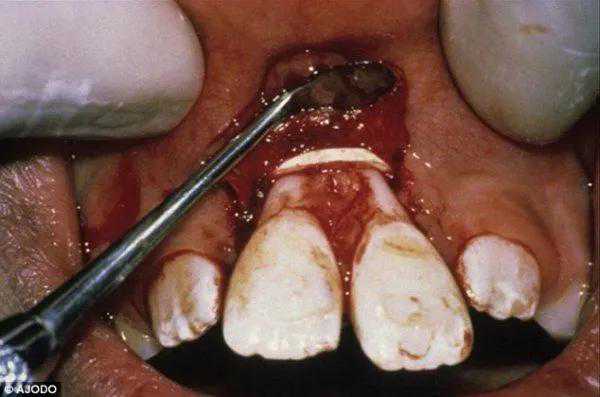

很多人觉得正畸又贵又麻烦,我家孩子只有两三颗牙不齐为什么要正畸?自己拿橡皮筋绑牙上不好吗?很多家长真的是敢想更敢做。真的就给孩子绑上橡皮筋。结果,很多孩子的牙齿松动脱落,最后还需要拔除,甚至需要手术把遗留在牙槽骨的橡皮筋取出来。。。

因为橡皮筋的力量很大,很容易破坏牙齿的牙周健康,牙槽骨吸收,牙根吸收,牙齿逐渐松动脱落。更可怕的是橡皮筋会滑脱,如果不及时取出来容易作为一个异物一直感染,甚至一直造成牙槽骨的感染。